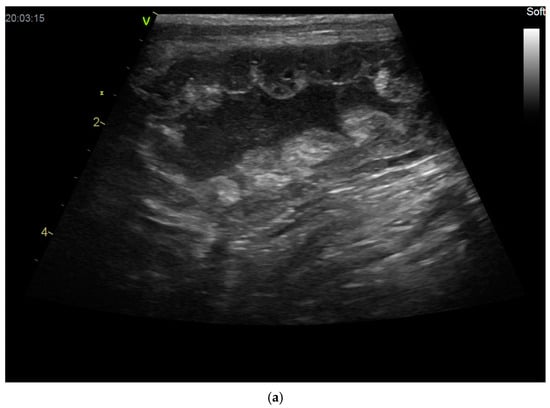

- Bigliardi, E.; Parmigiani, E.; Cavirani, S.; Luppi, A.; Bonati, L.; Corradi, A. Ultrasonography and Cystic Hyperplasia-Pyometra Complex in the Bitch. Reprod. Domest. Anim. 2004, 39, 136–140. [Google Scholar] [CrossRef] [PubMed]

- Quartuccio, M.; Liotta, L.; Cristarella, S.; Lanteri, G.; Ieni, A.; D’Arrigo, T.; De Majo, M. Contrast-Enhanced Ultrasound in Cystic Endometrial Hyperplasia–Pyometra Complex in the Bitch: A Preliminary Study. Animals 2020, 10, 1368. [Google Scholar] [CrossRef] [PubMed]

- Younis, M.; Mohammed, F.F.; Ragab, R.S.; Gohar, H.M. Ultrasonography and Pathological Evaluation of Cystic Endometrial Hyperplasia Pyometra Complex in Bitches and Queens with Related Ovarian Alterations. Glob. Vet. 2014, 13, 60–67. [Google Scholar]